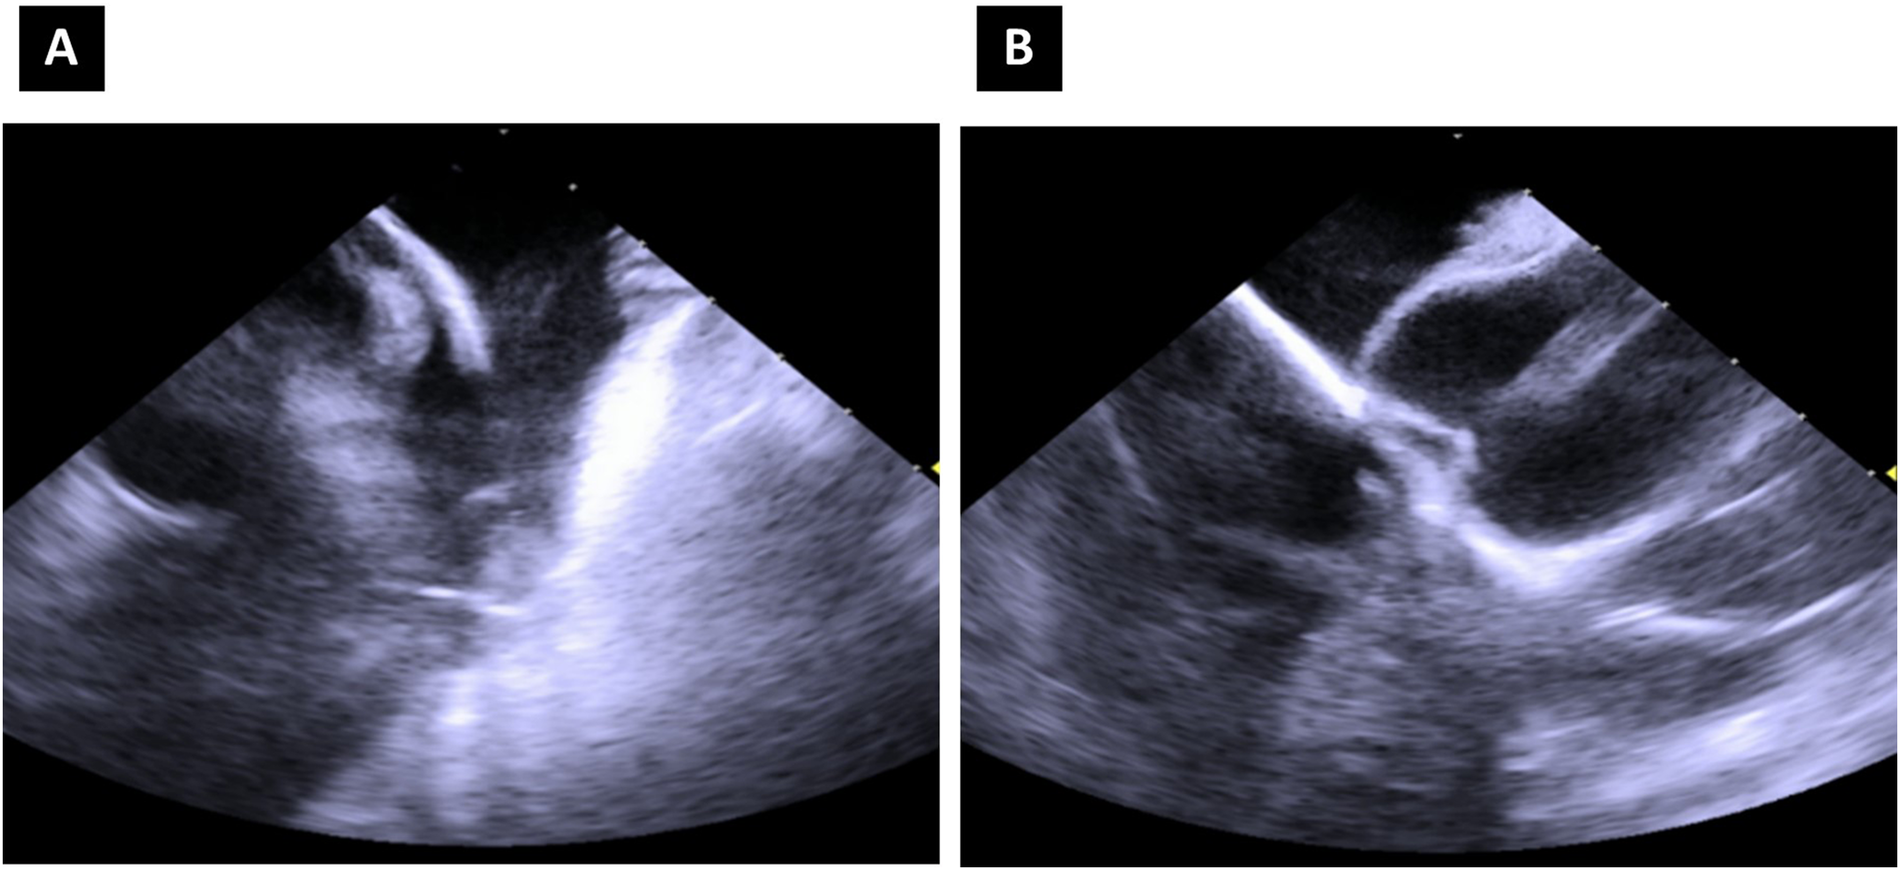

In patients presenting with PVCs, ablation target sites were localized using 12-lead ECG and earliest activation sites. The FARAWAVE catheter was positioned in the RVOT in basket configuration (Figures 1A,B), and adequate contact was confirmed with intracardiac echocardiography (Figures 2A,B) and by the presence of local electrogram signals recorded by the ablation catheter, which preceded the onset of the QRS complex on the surface ECG. Stable contact was maintained at the desired ablation site through the following steps. First, the sheath was positioned in the right ventricle, and the guidewire was advanced into one of the pulmonary arteries. The ablation catheter was then advanced in a closed position into the RVOT and subsequently deployed in a basket configuration. In this position, the catheter was gently and carefully maneuvered until the earliest ventricular local electrograms were found, usually just below the level of the pulmonary valve. The first set of applications was delivered at this point. After a slight further retraction of the catheter, a second set of applications was performed. All catheter movements were carried out under continuous fluoroscopic guidance. The PVC ablations ended with a 10-minute waiting period to assess the disappearance of PVCs.

Figure 2. Intracardiac echocardiography image of the pentaspline catheter in “basket” configuration, right ventricular outflow tract view (A) and mid-right atrium—“home” view (B).